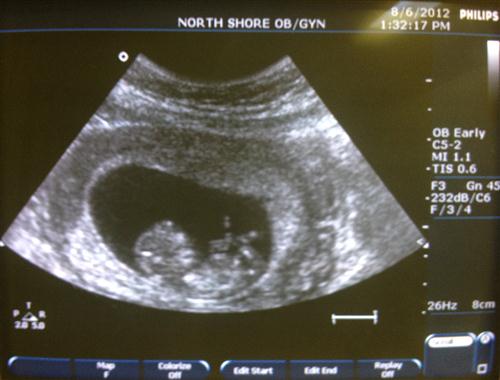

baby

Username: MommaDina

Last Update: 10/1/12

Photo(s): 1